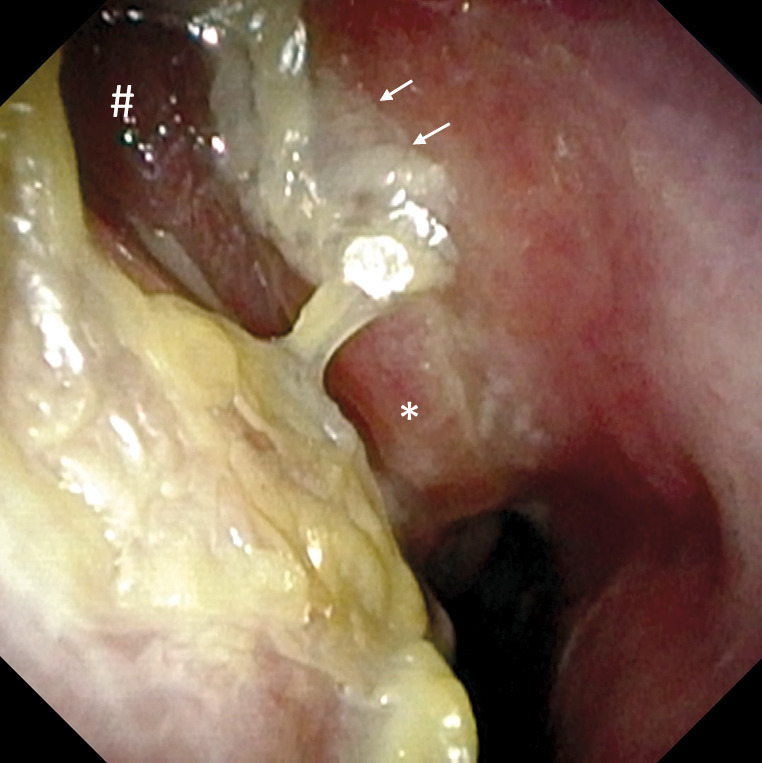

L’observation en nasofibroscopie montre des sécrétions mucopurulentes épaisses et, comme signalé plus haut, parfois des polypes.